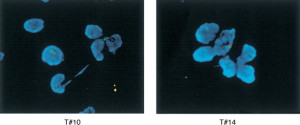

a destra: la zona 'calda' del CDKN2A